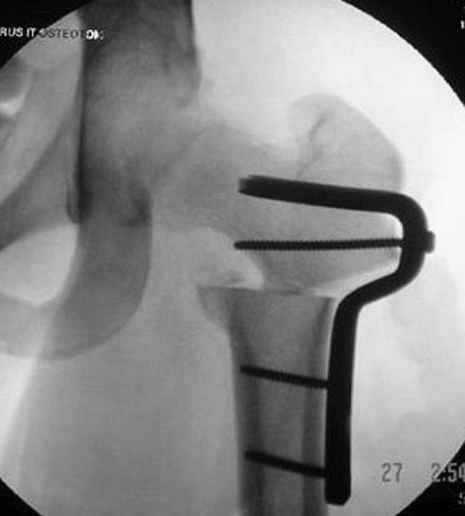

Отправитель: Alexander Chelnokov 23 Ноябрь 2004, 02:31

Если, например, доводится лечить больных с псевдартрозами шейки бедра, то надобность есть, и приходится. См. приложение.

Несколько снимков из моей коллекции, чтобы разьяснить, почему мы до сих пор делаем различные варианты остеотомии.

На рисунке N1 предоперационный план лечения ложного сустава шейки бедра- линия ложного сустава, угол и направление введения импланта, клиновидная остеотомия в градусах и миллиметрах, второй снимок после коррекции, расчет, на сколько удлиняется конечность и размеры импланта;

N3 рисунок окончательный снимок, после операции моя рентгенограмма должен выглядеть примерно как эта картина. На N4 снимке клин перед удалением; N5 послеоперации 3 нед.; N6 окончательная рентгенограмма.

(доложен в Ст. Петербурге 2003 и в Москве 2004)

варус при проксимальном отделе 95 градусной пластиной.